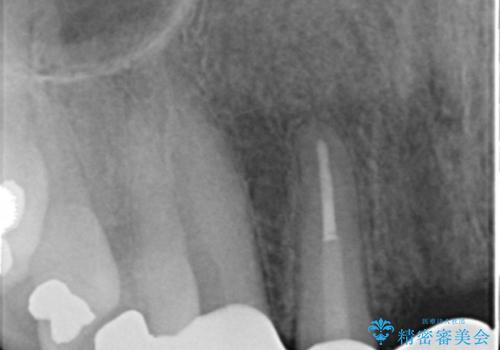

- お風呂場で転んで上の前歯が2本抜けてしまったことを主訴に来院された患者様です。

精査したところ、左上の側切歯(左上2)も破折しており保存不可能な状態でした。

左上の側切歯(左上2)を抜去し、右上の側切歯(右上2)の再根管治療後、セラミックのブリッジによる補綴を行いました。